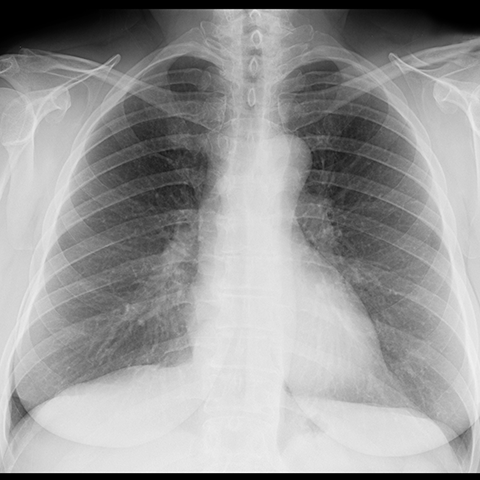

Normal anatomy of the lungs (CXR) [7 of 8]

Lines

Lines and Labels